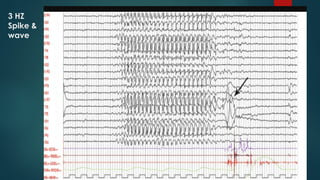

3 HZ

Spike &

wave

๏ต Absence seizures 3 HZ SW

๏ต Background EEG activity is normal.

๏ต There are inter ictal bursts of fronto central dominant

GSW and GPWS.

๏ต The frequency of these bursts tends to be more irregular

than the typical 3-Hz spike-and-wave bursts and varies

between 3 and 5 Hz

๏ต Photosensitivity is found in about 30% of males and 40%

of females